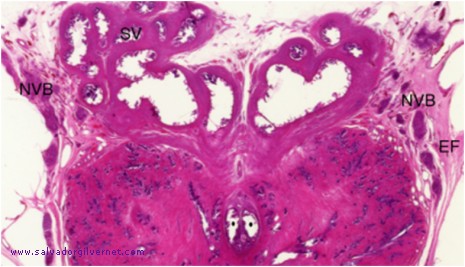

Detalle 2: Vesículas seminales (SV) y ampollas deferenciales. Conductos eyaculadores (puntos negros). Haces neurovasculares (NVB) con ganglios del plexo pelviano, perivesiculares y prostáticos. Hoja visceral de la fascia endopélvica (EF) atravesada por ganglios y nervios de los haces neurovasculares.

Pelvis fetal varón (8 meses)

• Serie H-4  Corte 50

• Sección frontal oblicua en un eje de inclinación dorso-ventral

Tinción HE

• ca. 1950

Celda seminal con vesículas seminales y ampollas deferenciales Pedículos neurovasculares vasoseminales y prostáticos. Próstata, uretra prostática con el relieve de la cresta uretral integrada por el haz muscular prostatouretral posterior (1). Fascia endopélvica (hoja visceral). Haces prostáticos neurovasculares. Músculos elevadores del ano. Esfínter uretral externo con sus componentes liso y estriado que abrazan a la uretra prostatomembranosa (2). Cuerpo esponjoso del bulbo uretral y músculo bulbocavernoso.